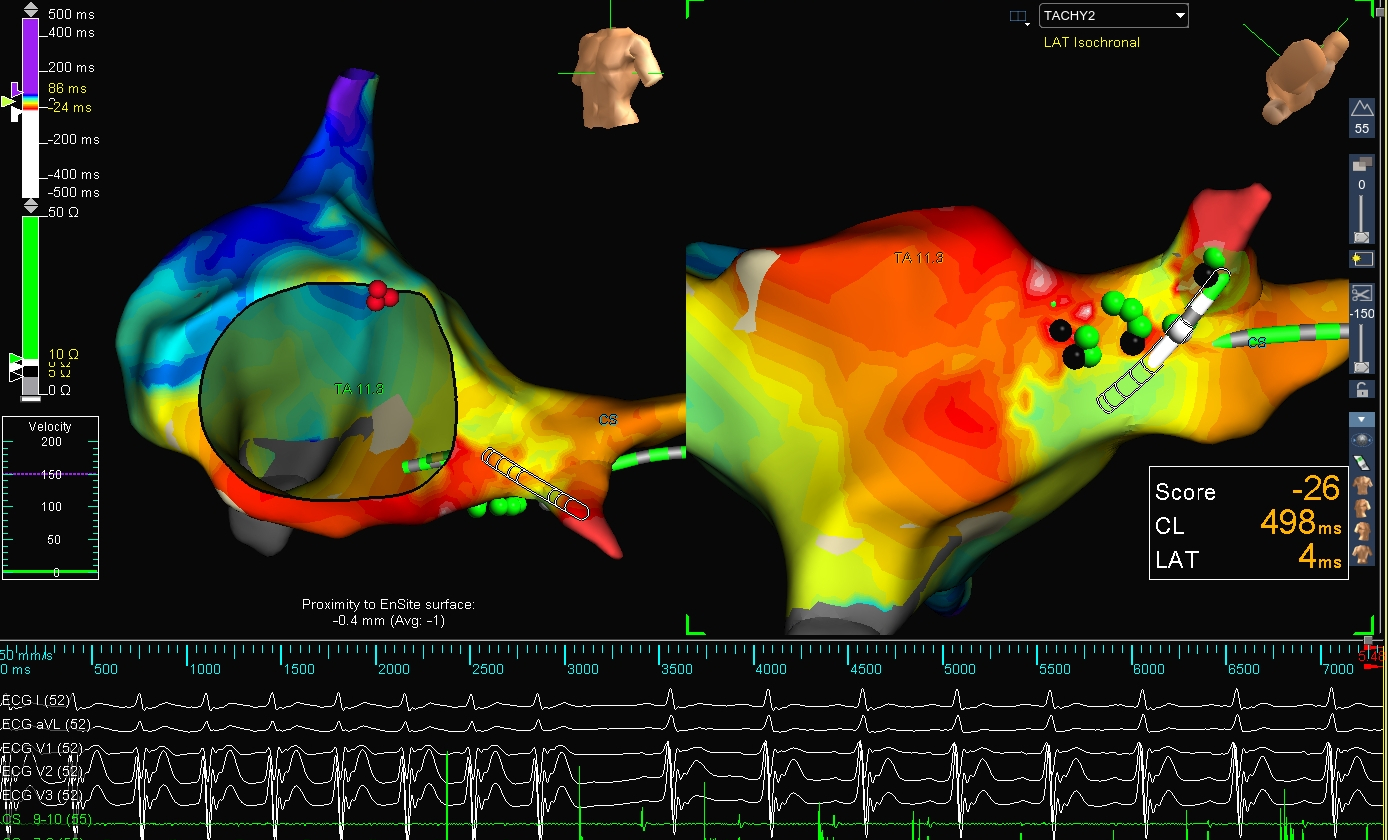

Short RP - Open window mapping

owm_1.jpg

Open window mapping

owm_2.jpg